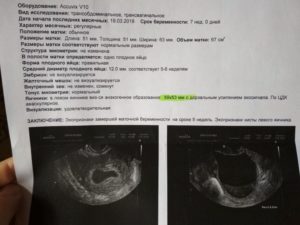

Желточный мешок в норме визуализируется с 6 до 12 недели беременности и представляет собой округлое тонкостенное анэхогенное образование в непосредственной близости от эмбриона. Его диаметр составляет 4-8 мм (на 7-ой неделе от 4-5 мм), постепенно увеличивается до 10 мм, и затем начинается его обратное развитие.

При ультразвуковом исследовании трансвагинальным датчиком желточный мешок определяется с 6 по 12 неделю беременности. Допускаются незначительные отклонения (до 2 недель) в любую сторону. Отсутствие на УЗИ желточного мешочка – неблагоприятный признак, свидетельствующий о серьезных нарушениях в течении беременности.

При проведении УЗИ врач оценивает расположение, форму и размер желточного мешка. Размеры желточного мешочка будут зависеть от срока гестации.

Нормы желточного мешка по неделям:

Важно помнить: размер желточного мешка быстро меняется на ранних сроках беременности. Незначительные отклонения не должны пугать беременную женщину и не могут быть основанием для постановки серьезных диагнозов.